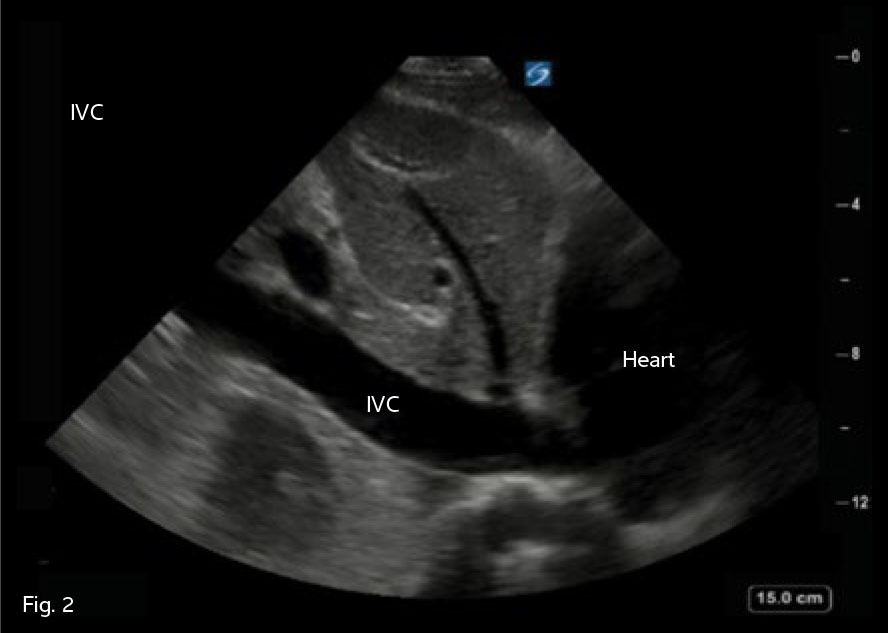

IVC Fig. 2